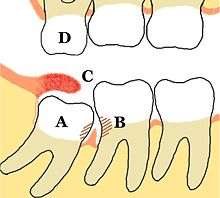

Impacted wisdom teeth are classified by the direction and depth of impaction, the amount of available space for tooth eruption and the amount soft tissue or bone that covers them. The classification structure allows clinicians to estimate the probabilities of impaction, infections and complications associated with wisdom teeth removal.[6] Wisdom teeth are also classified by the presence of symptoms and disease.[8]